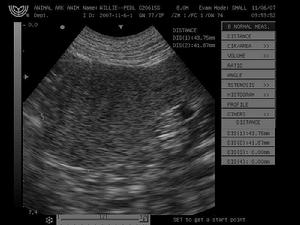

2.影像學檢查方法和比較 超聲方法簡便但機器設備和操作者的經驗可影響病灶的顯示一般直徑10mm以上的病灶是可以發現的區別病灶為實質性還是囊性是敏感的。此外超聲還能檢查腹部其他臟器有無累及如腎上腺腎臟盆腔等。放射性核素僅能顯示直徑大於20mm的占位病灶且形態顯示較差,定性較難MRI對脾臟內占位病灶的顯示決定於脾臟和病灶的信號強度,以及是否為瀰漫性如果病灶內有液化壞死則水分增加、T2延長,在T2加權圖像上產生高信號而在T1加權圖像上有時很難發現。順磁造影劑的套用可以縮短T1使病灶易於顯示影像檢查方法的選擇依次為超聲、CT、MRI和放射性核素上述方法的結合使用可相互彌補提高檢出率。